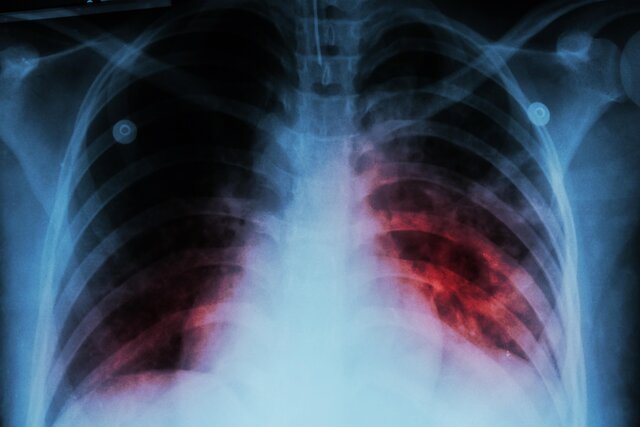

به گزارش ایسنا، دکتر قباد مرادی اظهار داشت: برآورد سازمان جهانی بهداشت از میزان بروز سل در کشور حدود ۱۱ مورد به ازای هر ۱۰۰ هزار نفر جمعیت است.

وی افزود: بر اساس دادههای ثبتشده، میزان کشف موارد سل در کشور بین ۷ تا ۸ در هر ۱۰۰ هزار نفر است. هنوز پاسخ قطعی به این پرسش که آیا برآورد سازمان جهانی بهداشت دقیقتر است یا میزان شناسایی ما کمتر از واقعیت است، مشخص نشده و در حال بررسی هستیم تا به پاسخ علمی و قطعی برسیم.

مرادی با اشاره به وضعیت کنترل بیماری سل در ایران، گفت: حتی اگر همان برآورد ۱۱ در ۱۰۰ هزار نفر را ملاک قرار دهیم، در مقایسه با کشورهای همسایه، ایران یکی از بهترین عملکردها را در زمینه کنترل بیماری سل دارد. تنها یکی دو کشور از حاشیه خلیج فارس با جمعیت کمتر در این زمینه شرایط بهتری دارند که طبیعتا کنترل بیماری در جمعیتهای محدود سادهتر است.

رییس مرکز مدیریت بیماریهای واگیر وزارت بهداشت افزود: در شرق کشور، دو کشور همسایه با یکی از بالاترین میزان بروز سل در جهان قرار دارند و یکی از آنها تخمینی بیش از ۲۰۰ مورد به ازای هر ۱۰۰ هزار نفر جمعیت دارد. با توجه به وجود حدود ۵ میلیون نفر مهاجر از این کشورها در ایران، حفظ این سطح از کنترل بیماری، دستاوردی بسیار ارزشمند برای نظام سلامت محسوب میشود.

مرادی خاطرنشان کرد: اگر بتوانیم اثبات کنیم که میزان بروز سل در کشور به کمتر از ۱۰ مورد در ۱۰۰ هزار نفر رسیده است، بر اساس تعریف جهانی حذف سل، ایران در جمع کشورهای پیشرو و موفق دنیا در کنترل این بیماری قرار خواهد گرفت.